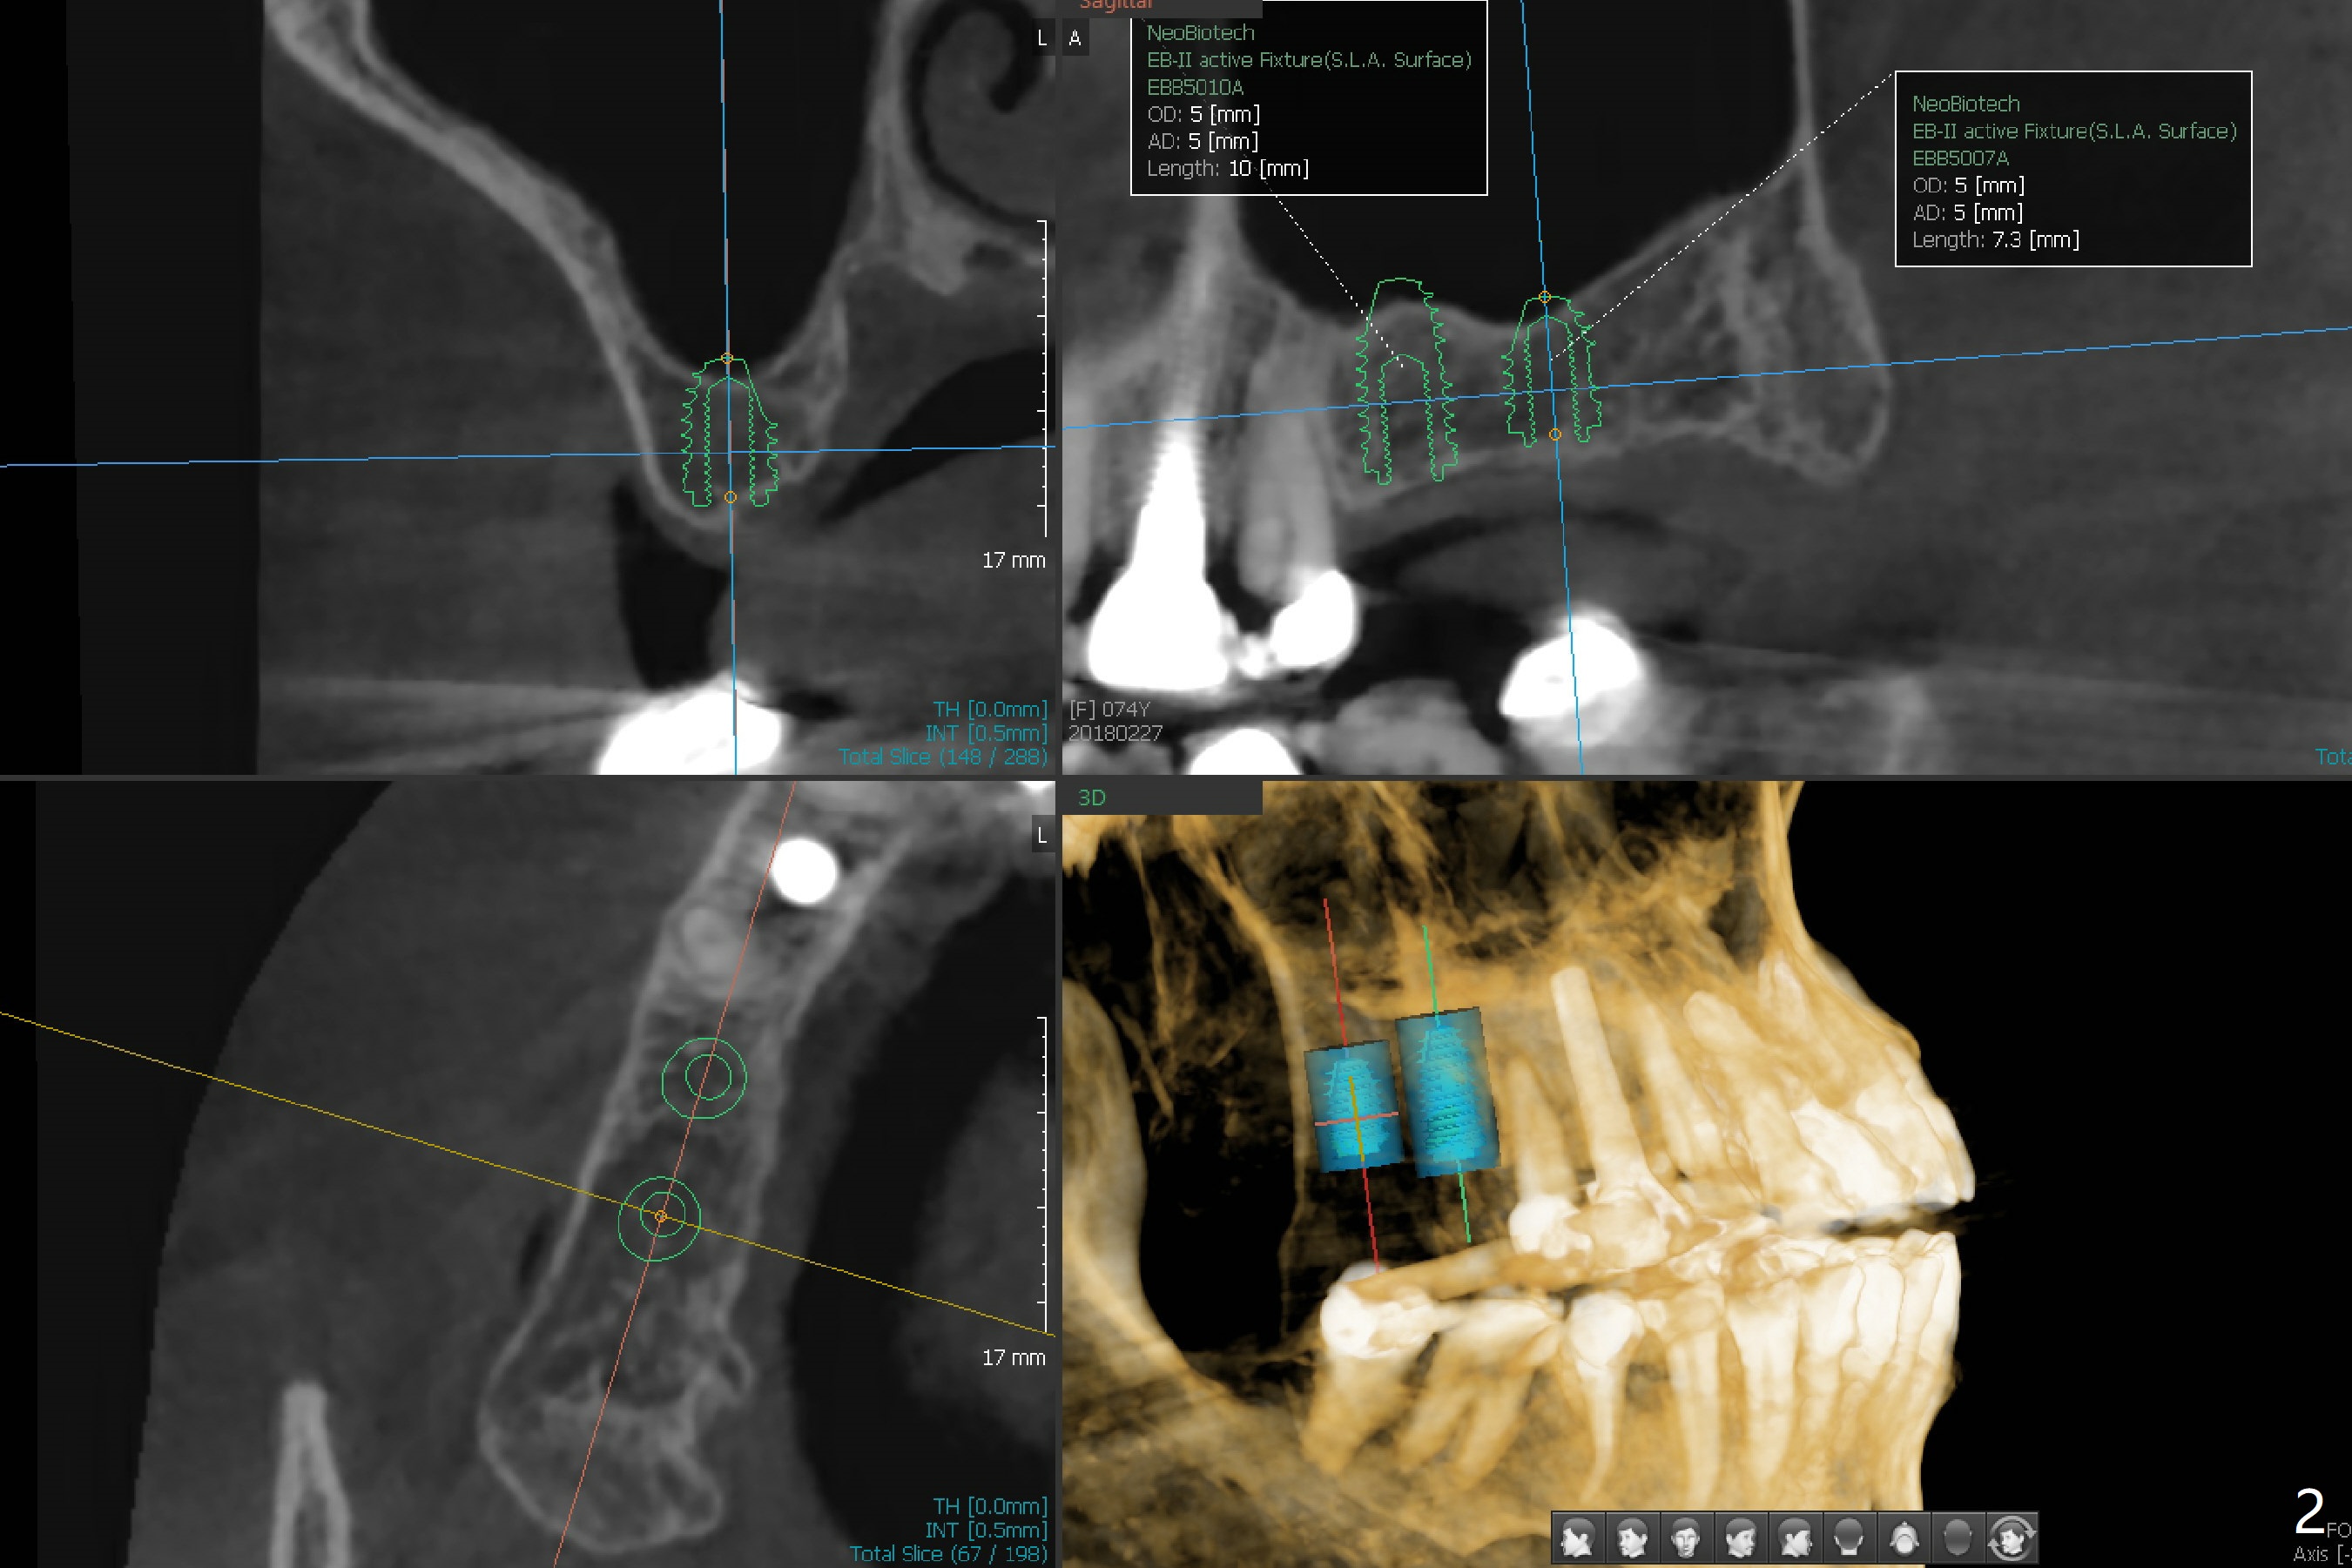

A 74-year-old woman needs cementation at #18 and 19 because of missing teeth at #2 and 3 (Fig.1). It will be efficient to place 2 implants with guided surgery. A challenge is limited bone height (Fig.2); sinus lift is required. After finishing osteotomy, remove the guide for sinus lift using Sinus Lift Master kit. Return the guide and finish implant placement.